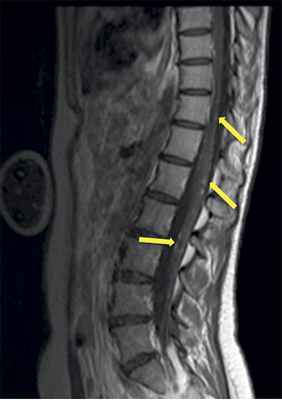

Учитывая темп развития симптомов, был заподозрен злокачественный характер опухоли. В день поступления (02.03.16) пациентке выполнена МРТ головного мозга и спинного мозга с контрастным усилением. Была выявлена диссеминация процесса с появлением опухоли в левом внутреннем слуховом проходе, множественных очагов патологического накопления контрастного вещества оболочек спинного мозга. Динамика распространения первичного очага и метастазирование представлены на рис. 1 и 2.

Рис 2. МРТ от 02.03.2016 - метастазирование опухоли по оболочкам спинного мозга (указаны стрелками).